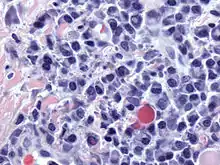

Dutcher body (plural Dutcher bodies)

- (microbiology) One of the periodic acid-Schiff reaction-positive nuclear inclusions, containing immunoglobulin, that are either invaginated into or overlying the nucleus.